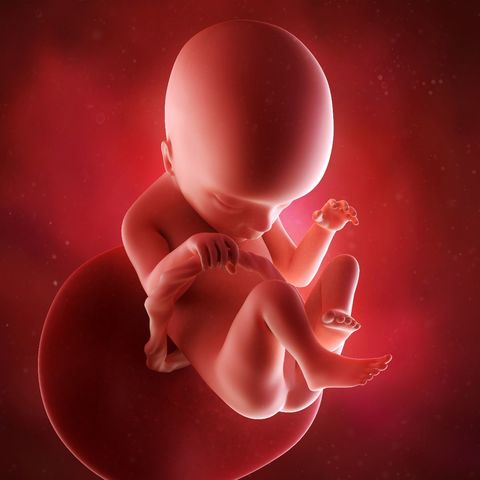

• 35 Semanas de Gestación

35 Semanas de Gestación

Son más frecuentes los movimientos respiratorios, aun que todavía no hay aire en los pulmones